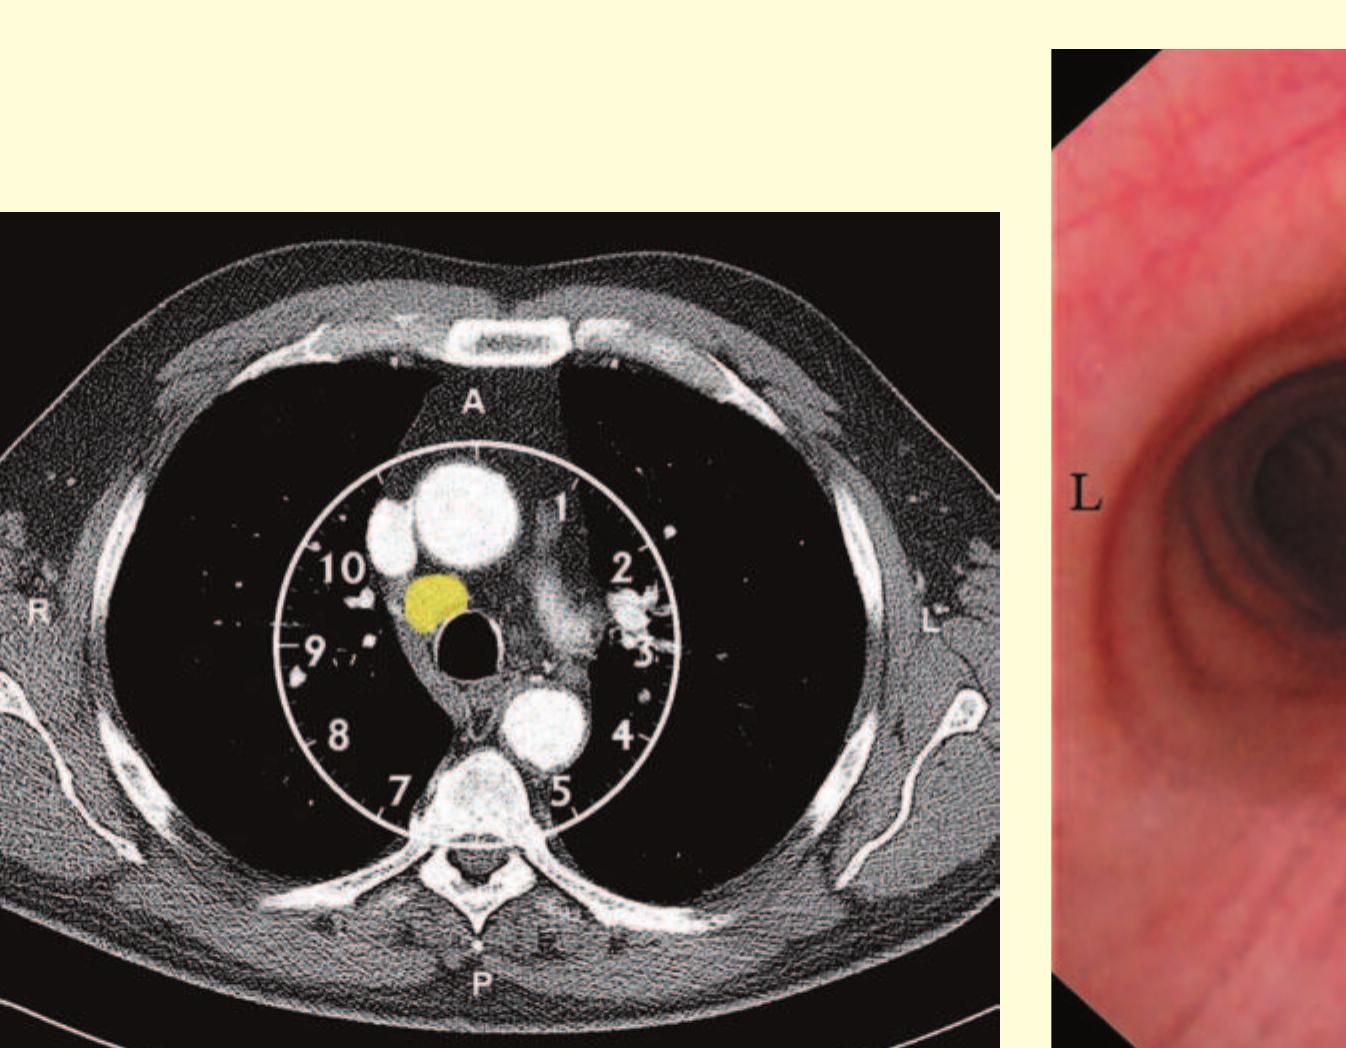

- The bronchoscope is then rotated anticlockwise by 150° to examine the subcarinal lymph nodes (station 7), extending down to the distal margin of the bronchus intermedius.